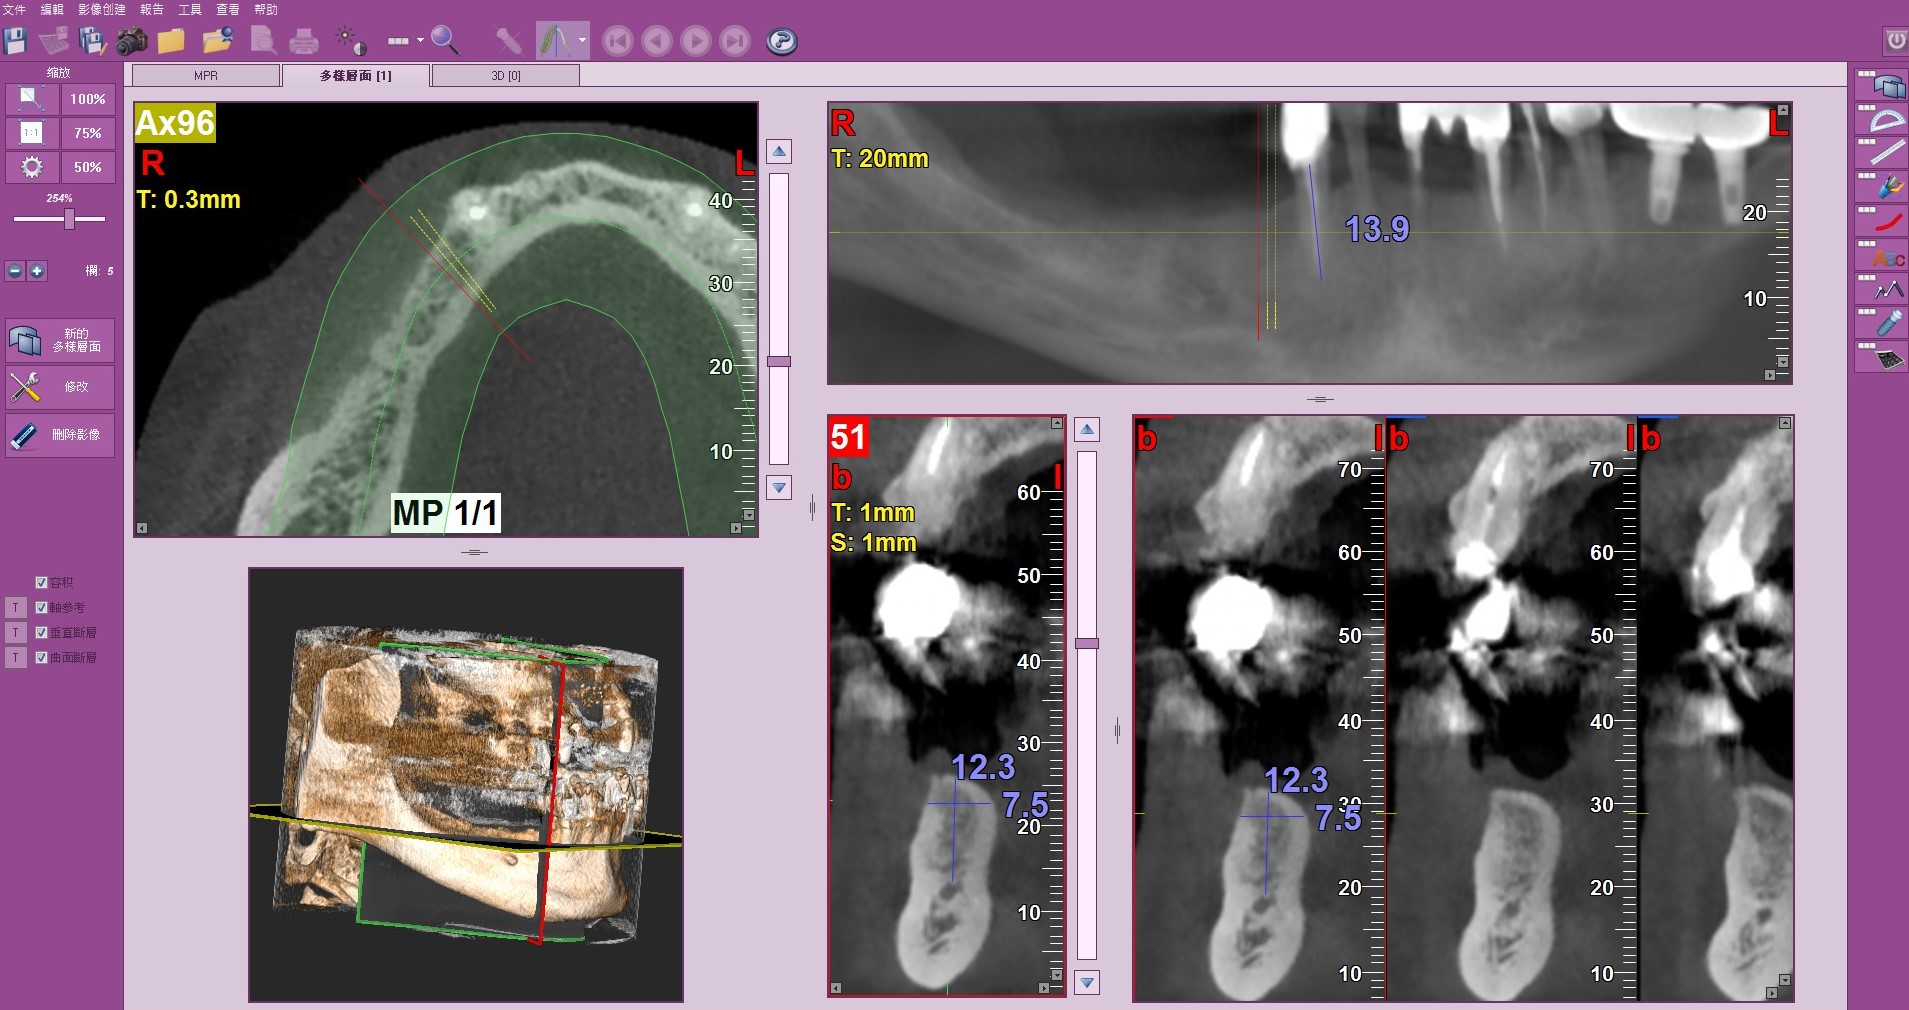

先在電腦斷層(CT) 上研究解剖構造與骨量

把相關CT資料與實體3D模型結合,在植體設計軟體上進行植體位置設計